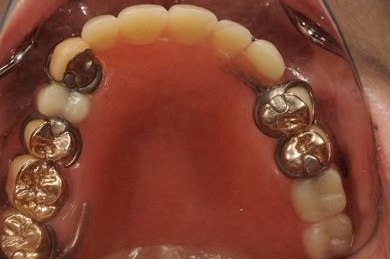

インプラントの症例写真 IMPLANT

インプラント治療+オーバーデンチャー

| 治療方針 | 下顎に2本インプラントを埋入し、アタッチメントをつけて、オーバーデンチャーを装着し、はずれにくく、安定した義歯を装着する。 | ||||||||||||||||||||||||||||||||

| 治療内容 | インプラント2本(テンポラリーインプラント)、アタッチメント、コバルトクロム床オーバーデンチャー | ||||||||||||||||||||||||||||||||